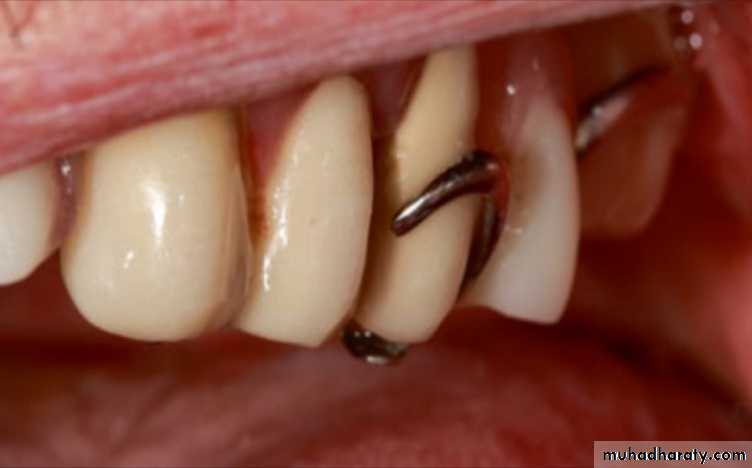

The guiding planes should be carefully examined, and if there is a minor incongruity, the RPD may seat after preparing the guiding planes.A rest and clasp assembly not fully seated will

probably apply nonaxial forces to the abutment tooth